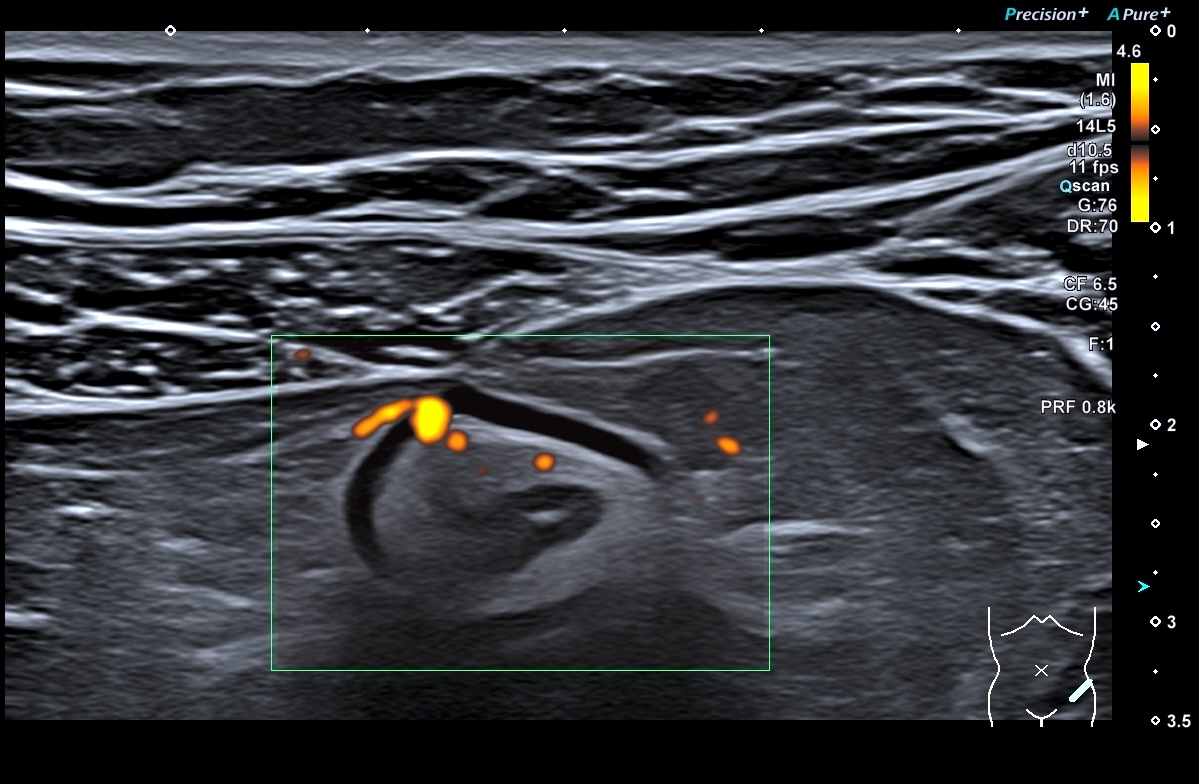

Sigmoïde basse fréquence

Même lésions avec la sonde haute fréquence, épasissement de 7 mm prédominant à la 3 ième couche, c'est à dire la sous muqueuse, hyperéchogène

les signes extra-digestifs sont peu marqués (graisse peu infiltrée, faible activité doppler, voir nulle)

Sigmoïde coupes transversales et longitudinales et doppler haute fréquence

En doppler énergie

Ci-dessus, images de la paroi du sigmoïde avec la sonde haute fréquence. On a toujours les mêmes caractéristiques

La graisse est peu infiltrée, Doppler plus marqué (Limberg 2 voir 3)

Le score de Milan est de (4,5 x 1,4+2)= 8,3 donc la maladie reste active, elle s'est même dégradée. (Score passé de 5.74 à 8.3)